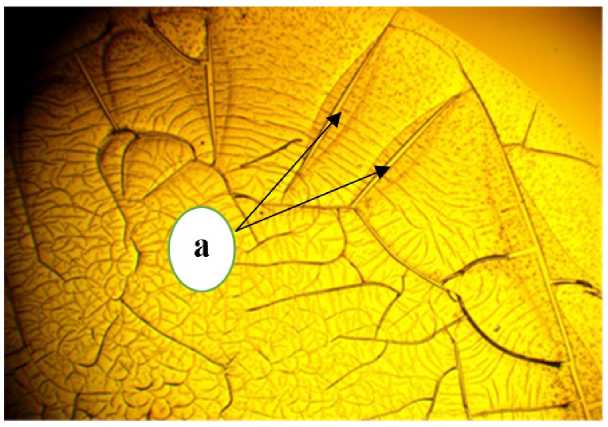

Радиальный тип фации традиционно используется как нормативный показатель при исследовании исходной фации сыворотки. Частично радиальный тип фации, демонстрирующий высокую упорядоченность ключевых структурных элементов (например, двойная фация, как показано на рисунке 1), может рассматриваться как вариант нормы.

Рисунок 1 – Фрагмент фации сыворотки крови больного теленка: частичнорадиальный тип; а - двойная фация, ув. х 10